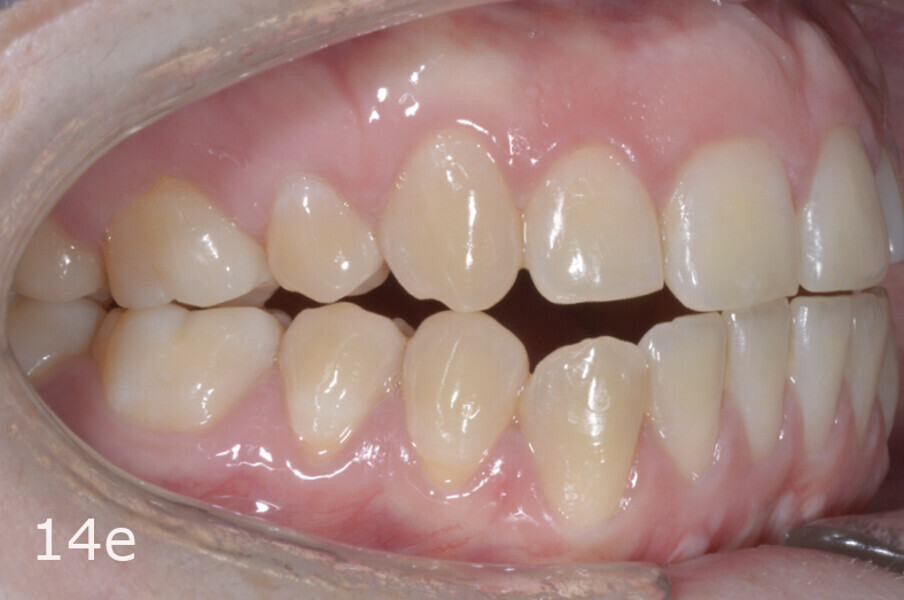

The 23-year-old dolichofacial female patient complained of not being able to chew properly. Facial examination showed a convex profile, an enlarged lower facial height, and a skeletal Class III malocclusion (Figs. 1–3). Intra-oral examination revealed an Angle Class III right subdivision malocclusion, anterior open bite, no overjet and a maxillary dental midline deviated about 3 mm to the right compared with the mandibular dental midline (Fig. 4). The panoramic radiograph confirmed previous extraction of the maxillary right first premolar and the presence of all four third molars (Figs. 5 & 6).

The treatment objectives included closing the anterior open bite, achieving a bilateral Angle Class I relationship and a proper overjet and overbite, correcting the midline discrepancies, and achieving a profile harmonisation. The treatment plan consisted of orthodontic camouflage treatment with asymmetric distalisation in three of the four quadrants using Invisalign aligners (Align Technology) and third molar extraction. The Invisalign Comprehensive package was chosen, and 63 pairs of aligners were used (Figs. 7–10). Each aligner was worn for 20 hours a day for one week each. The use of Class III elastics on both sides was indicated. Afterwards, ten refinement aligners were needed to improve the interdigitation on the right side (Figs. 11 & 12).

The total treatment time was 15 months. An Angle Class I relationship was established along with adequate anterior and canine guidance, establishing a functional occlusion. This not only ensures optimal masticatory function but also protects the teeth and the temporomandibular joint from excessive force. Maxillary and mandibular fixed retention were installed at the end of the treatment (Figs. 13–19).